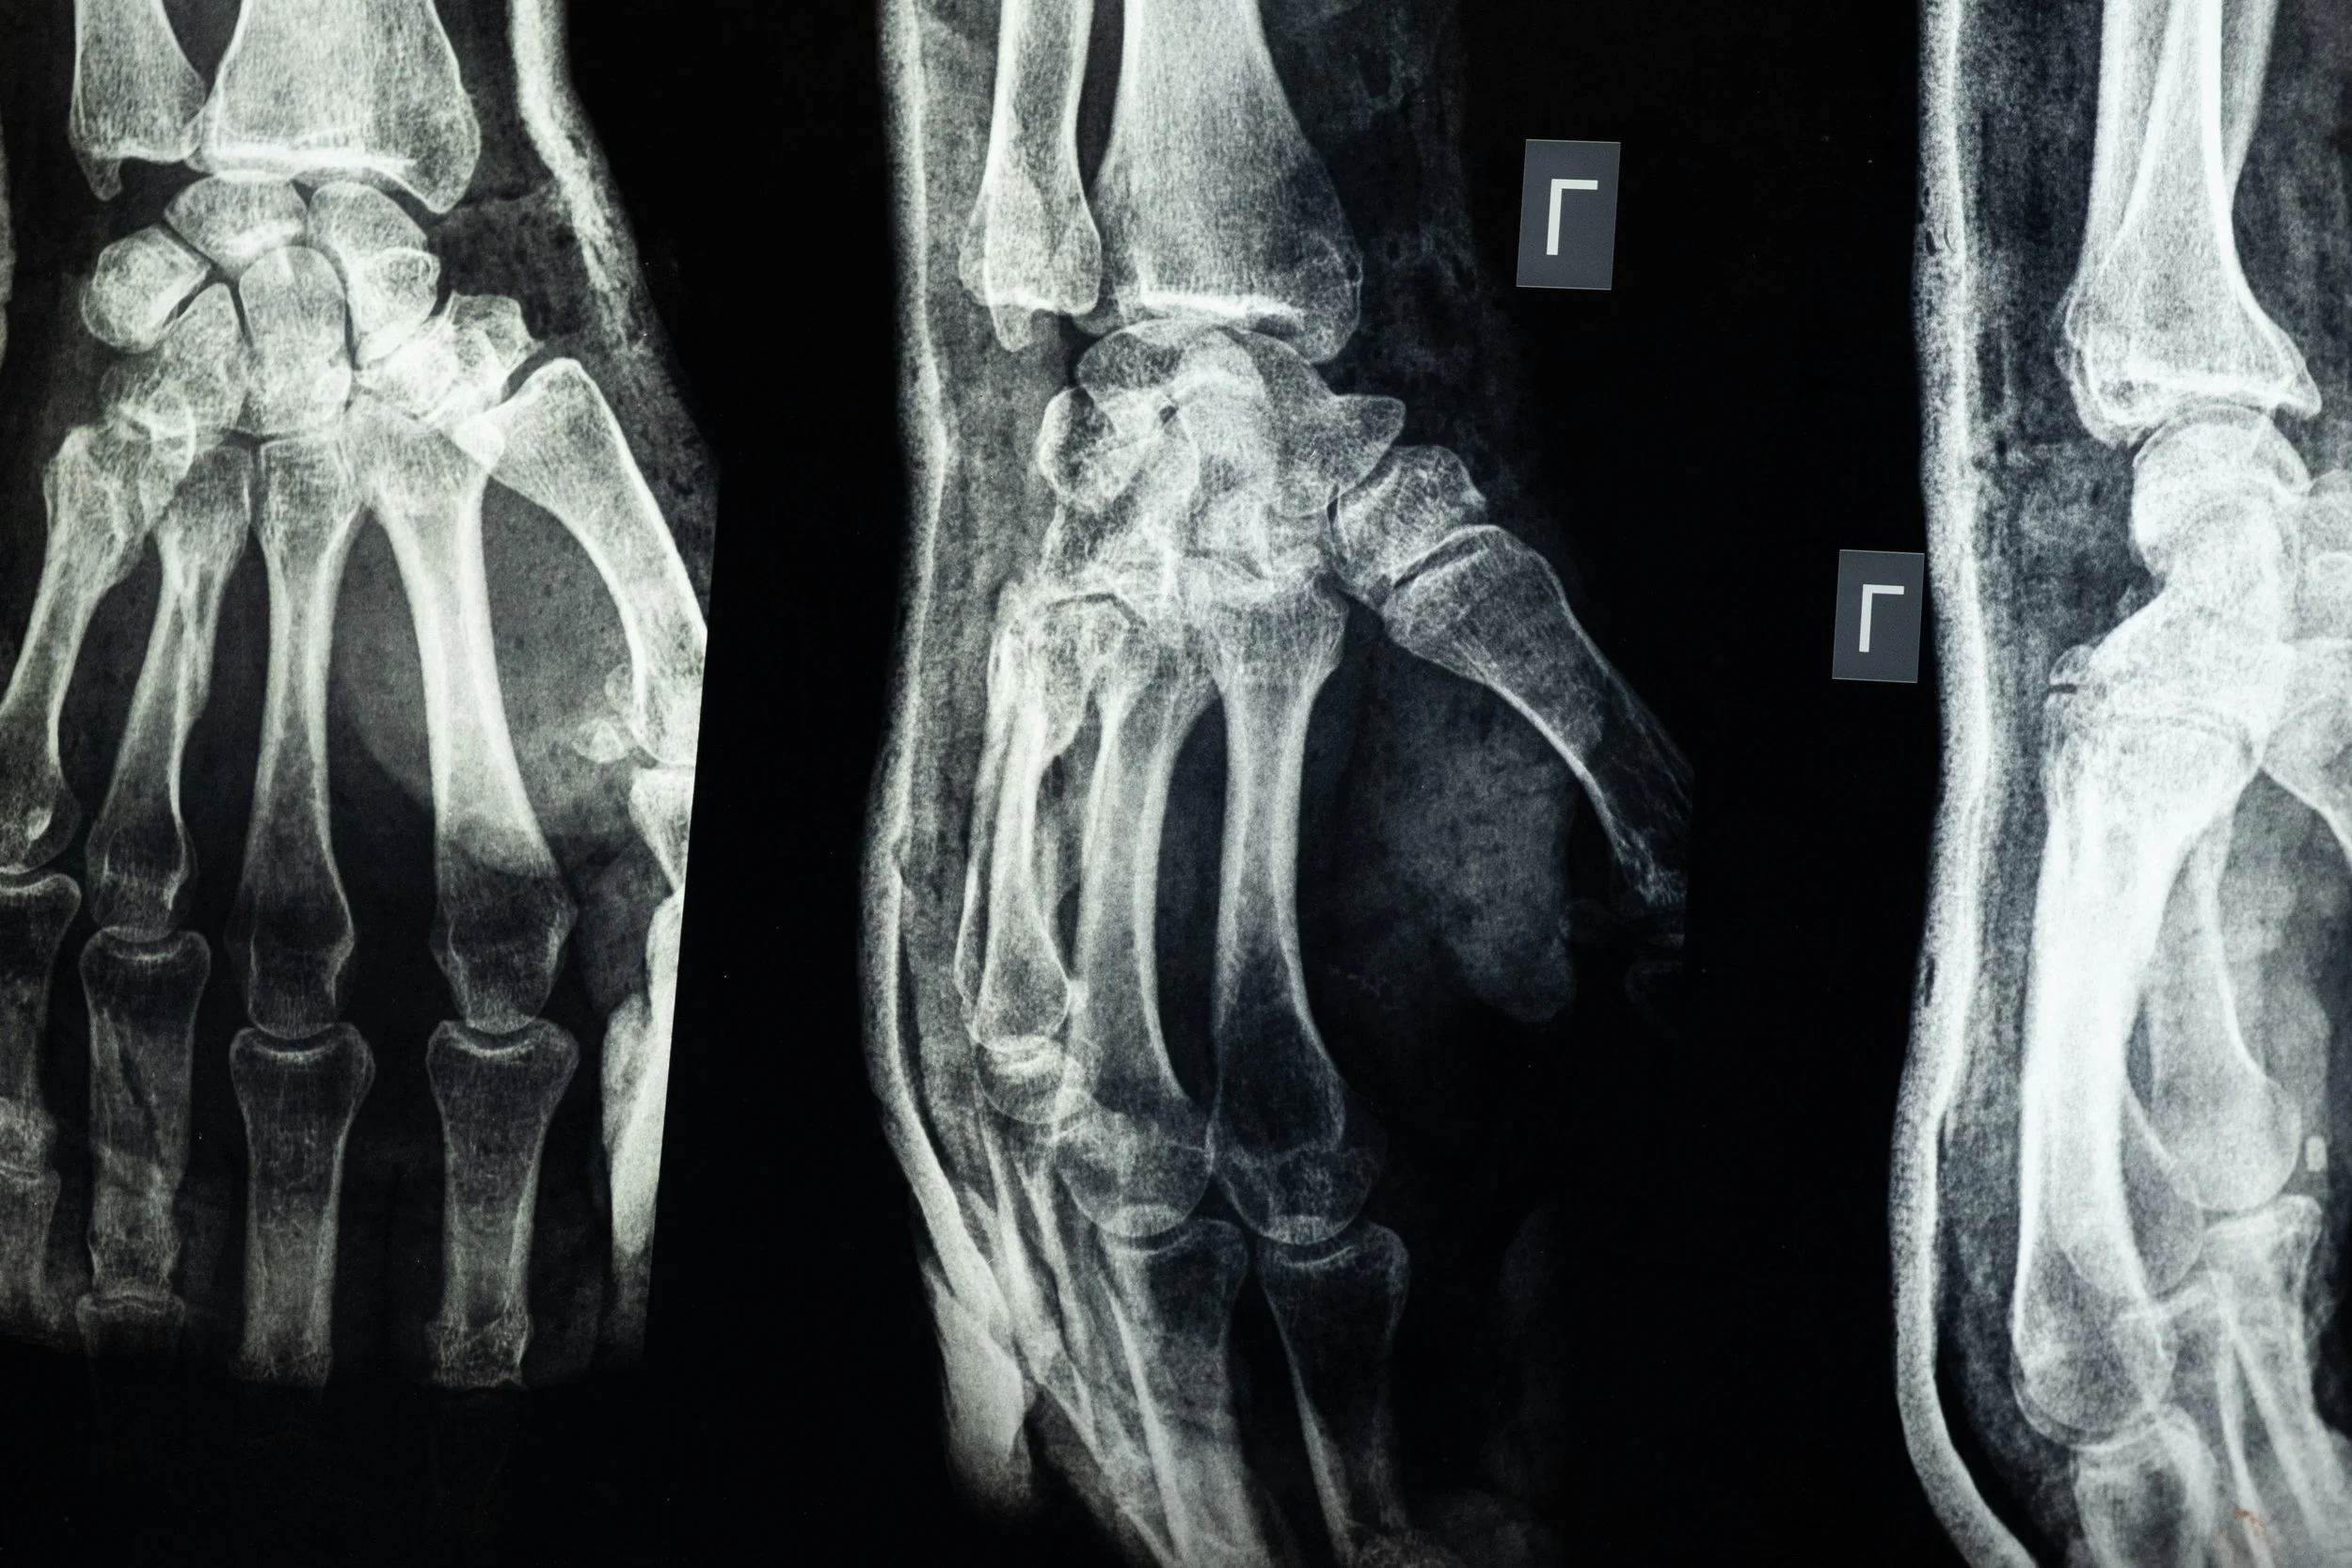

Osteoporosis is more than low bone density—it's a chronic condition that increases fracture risk even with minor trauma. Common fracture sites include the spine, hip, and wrist. Most of the time, fractures occur with a fall, but can also occur with heavy lifting (these are compression fractures in the spine). Osteoporotic fractures do not typically occur spontaneously (like with day-to-day normal activities). Hip fractures, especially can significantly affect long-term health and independence, which is why prevention is priority number one.